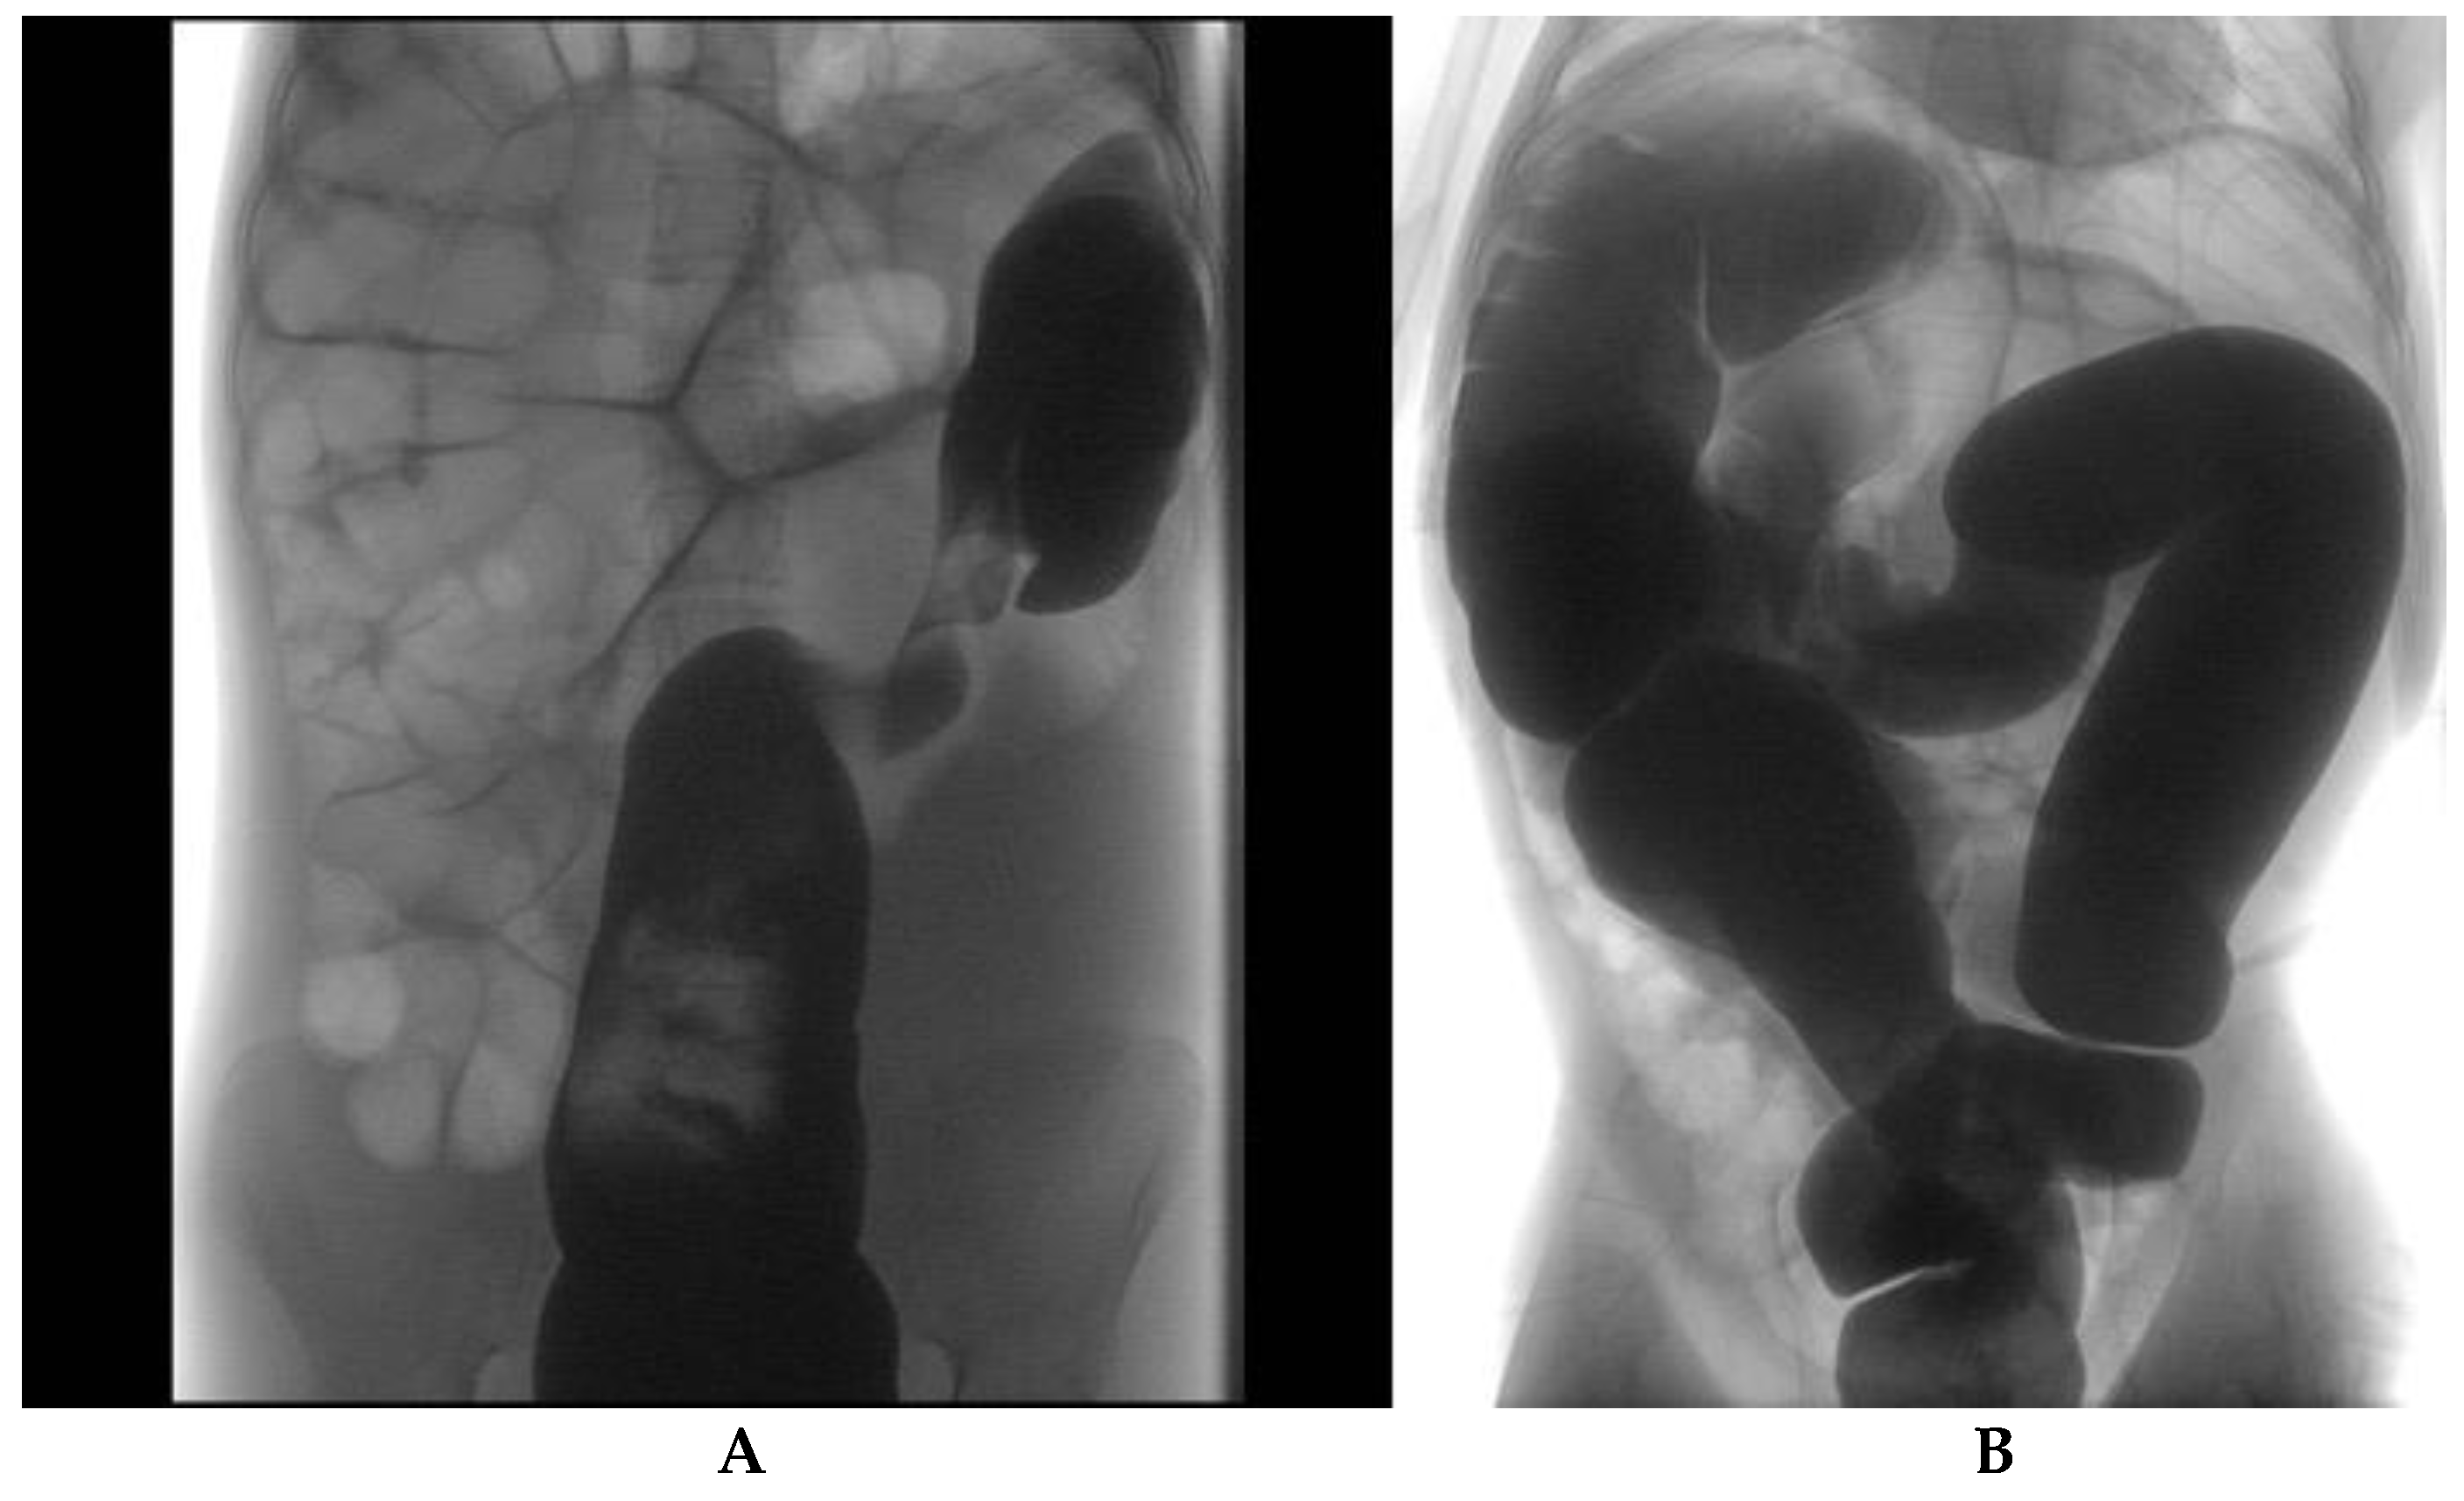

3.2. Instrumental Results